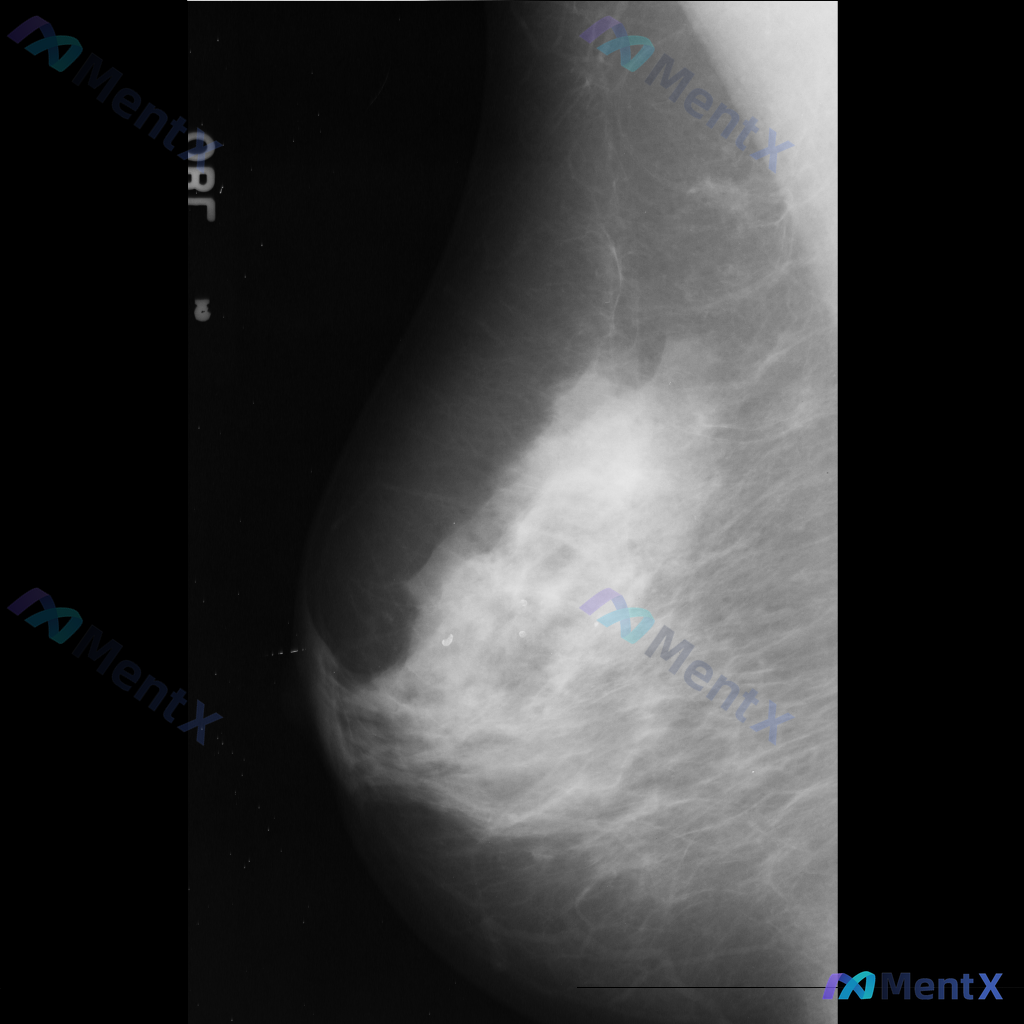

整理到一张乳腺钼靶影像的讨论资料,右乳可见一处病灶。 想先请大家看看:针对这张影像的异常表现,用什么术语描述最准确全面?另外结合征象,第一反应会往哪个方向考虑?

整理到一张乳腺钼靶影像的病例资料,影像表现如下: - 乳腺中央区域可见边界模糊、形态不规则的致密影 - 内部密度较高,与周围乳腺组织界限不清 - 可能存在结构扭曲或毛刺样改变 - 未见明确的良性钙化或其他典型良性征象 单看这组影像描述,大家第一反应会往哪种情况考虑?